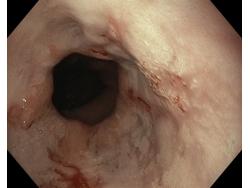

Choroba refluksowa